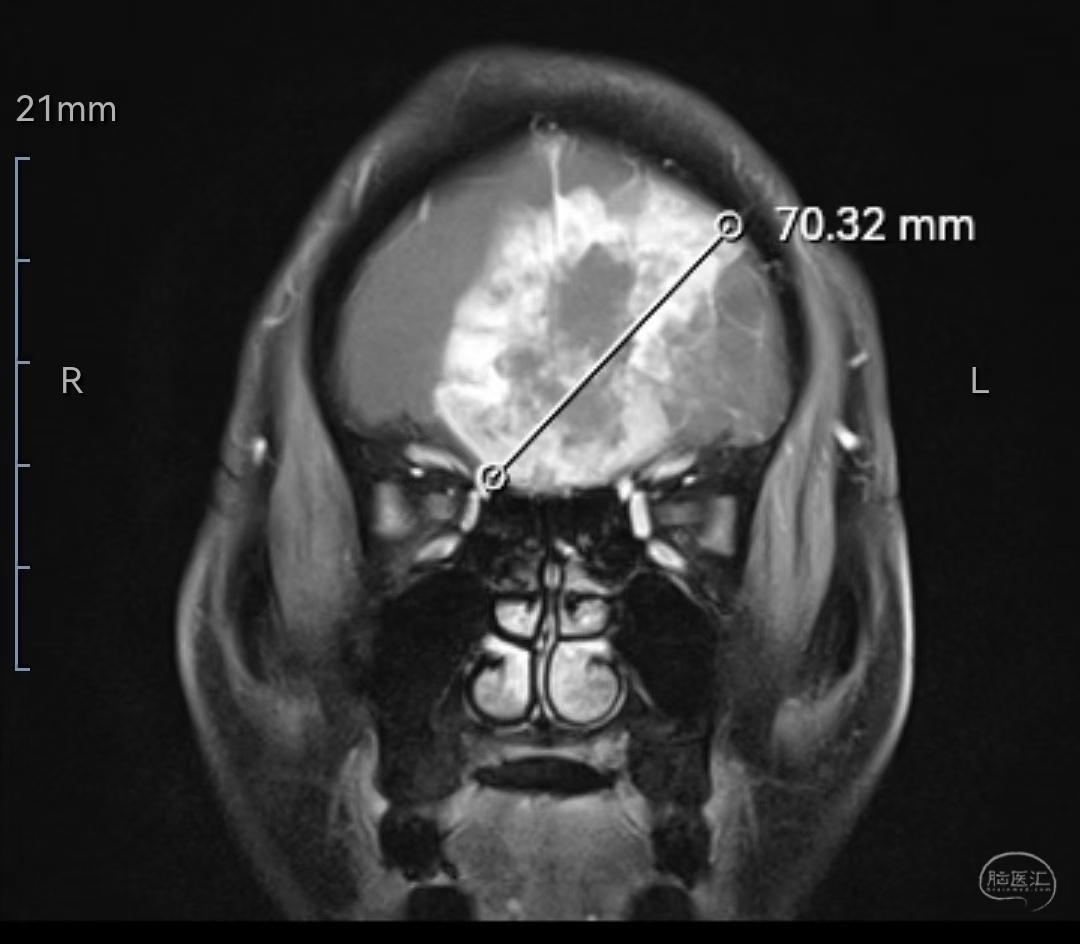

MRI增强冠状位示肿瘤明显强化,位于双侧额叶,左侧为主